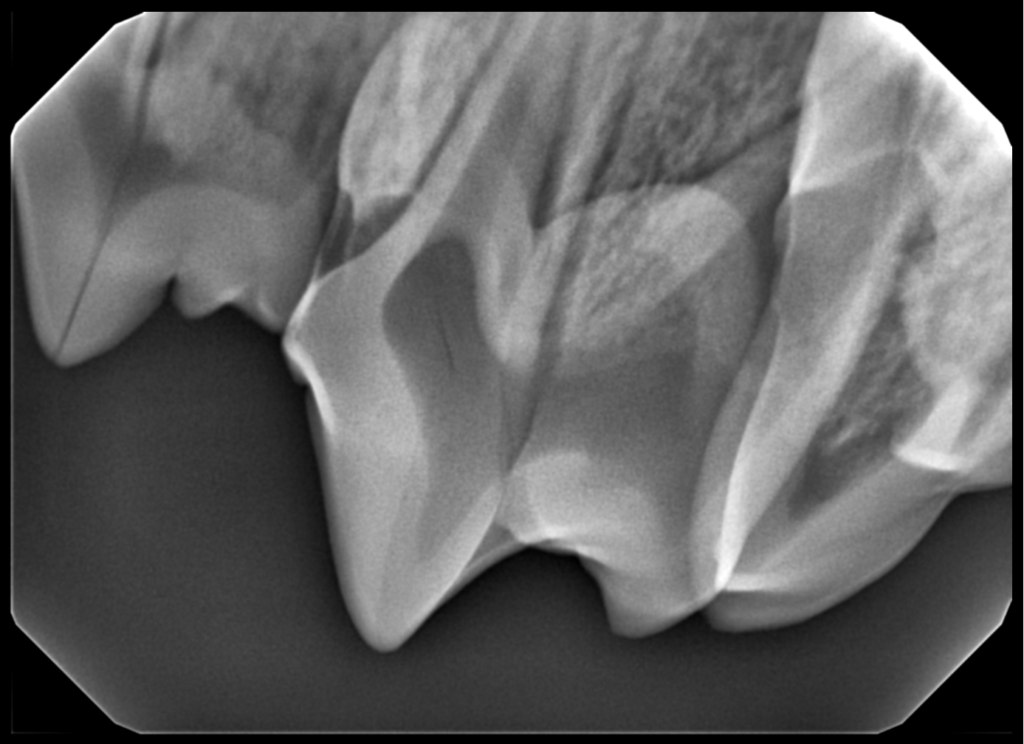

Interpretation of Dental Radiographs in Dogs and Cats, Part 1 Veterinary Dental X Ray Cpd Get all the help you need with your dental patients in this easy to attend, fully guaranteed, online mini series™ from cpd solutions Find a course right for you and enrol today. Our wide range of veterinary dentistry courses cover everything from preventative care, dental clinics, and. This learning series, with rachel perry, is suitable for both vets and vet. Veterinary Dental X Ray Cpd.